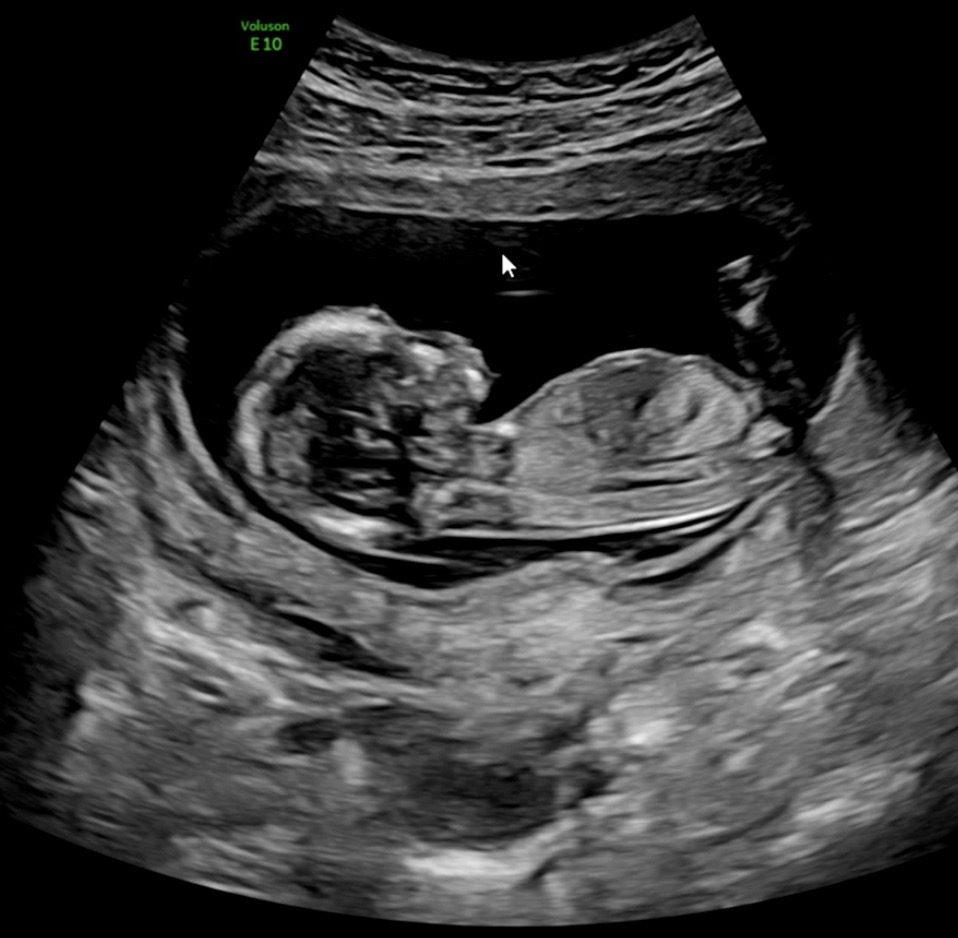

13주각도법 한번 봐주세용

13주0일입니다.. 아들일까요 딸일까요 ?! 자유롭게 투표 부탁드려요ㅠㅠ넘궁금하네요